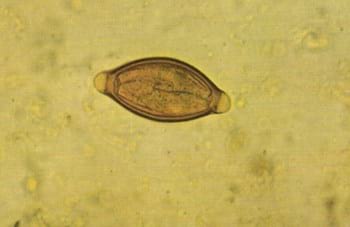

coproscopía ya que los huevos de los parásitos de este género son de

morfología inconfundible.

Huevo de Trichuris spp